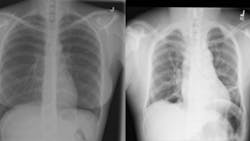

The complexity of medical images such as X-ray or lymph node scans presents a significant challenge for deep learning-based vision systems and anomaly detection, according to the authors of the research paper, “Anomaly Detection in Medical Imaging With Deep Perceptual Autoencoders” (bit.ly/3Goojkv/), because these anomalies strongly resemble normal images.

To test the new method, the researchers used the model to detect metastases in lymph nodes using the Camelyon16 dataset (www.camelyon16.grand-challenge.org/) and a subset of the NIH dataset for the detection of abnormalities in chest X-rays (bit.ly/NIHCC-XRAY).

The researchers’ model achieved 93.4% success on the lymph node scan analysis and 92.6% success on the X-ray scan analysis, outperforming current state-of-the-art methods by 2.8% and 5.2%, respectively. The researchers disclosed the source code for all their experiments.